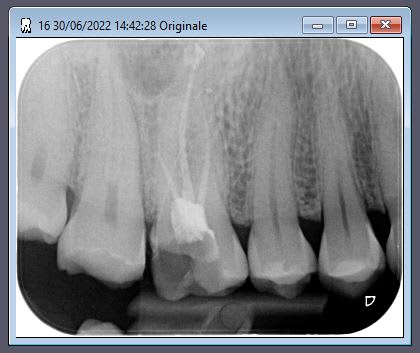

La sur la 16 d'une jeune de 25 ans, toujours hier probablement au tarif secu, bon bin ca je veux pas faire:

Iopxvy9w3cxt7v7cosx8mqu1pv5n - Eugenol